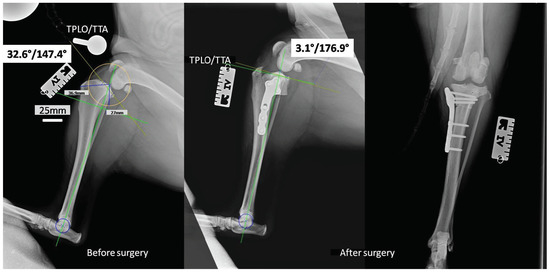

2.2. In Vivo Study

4.8. Tibial Plateau Leveling Osteotomy (TPLO)

4.9. Radiological Examinations